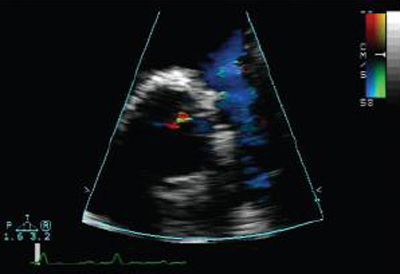

Doppler in a patient with pulmonary regurgitation following repair of tetralogy of Fallot. The patient has a restrictive right ventricle, and Doppler shows evidence of restriction with an antegrade ‘A’ wave in the pulmonary artery

From: Chaturvedi RR, Redington AN. Heart. 2007 Jul;93(7):880-9; used with permission